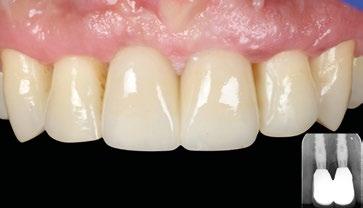

A los 9 meses se entrega la prótesis definitiva de metal-cerámica, que se encuentra con perfiles ya correctamente modelados y maduros. La comparación entre la situación inicial y la final resalta cómo el restablecimiento solo de la parte supraósea ha sido suficiente para compensar un importante déficit volumétrico, sin necesidad de recurrir a complejas reconstrucciones óseas, cuyo resultado suele ser poco predecible. 

Entrega de la prótesis definitiva de metal-cerámica.

Comparación entre la situación inicial y final.

Radiografías finales de la arcada superior.